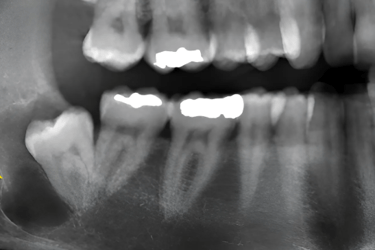

At smile center, our exams are completley free and include basic x-rays. Here we will point out exactly what you need, why, and how much and how many visits It would take.

We use 3D imaging and digital gscanners to plan precise extractions,

reducing swelling and healing time for better long-term results.